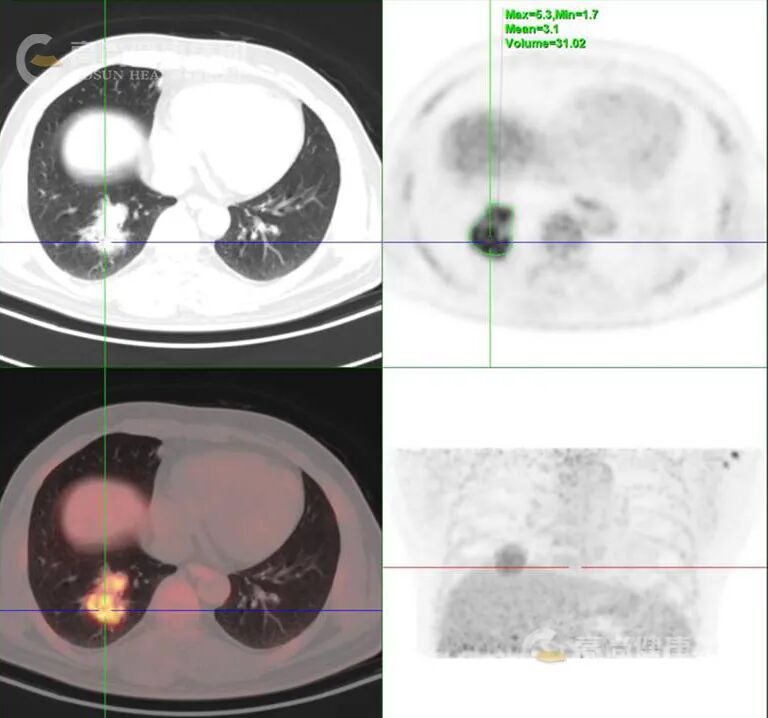

代谢活性特点:MALT 淋巴瘤作为低度恶性肿瘤,FDG 代谢常呈轻度至中度增高,SUVmax 范围多为 2.6-8.3(中位约 6.0),低于侵袭性淋巴瘤类型。

鉴别诊断价值:PET/CT 全身成像有助于区分原发性肺淋巴瘤与继发性肺部受累,且显示大多数肺部 MALT 淋巴瘤病灶存在 FDG 放射性摄取增高,但需注意与其他可导致放射性浓聚的肺部疾病(如肺癌、炎症、结核等)鉴别,需密切结合 CT 影像特征。

以下是肺部 MALT 淋巴瘤 PET/CT 典型表现的总结表格: